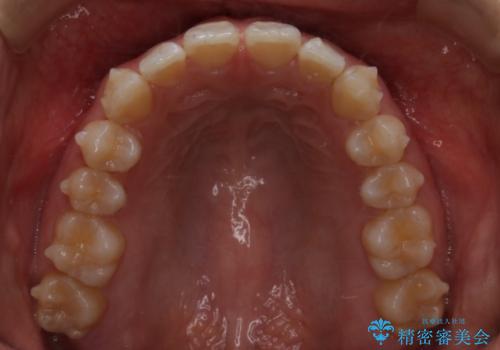

インビザライン矯正 前歯のすきっ歯を治したい

- 上顎の前歯のすきっ歯を治したいとのことで来院されました。

前歯の隙間を閉じる矯正治療の場合、インビザライン適用症例のためインビザラインによる治療をご提案しました。

後戻り防止のため、上唇小帯切除も併用しています。

上唇と歯ぐきを結ぶひも(上唇小帯)が長いと、前歯に隙間が空いてしまうことがあります。今回は隙間を確実に閉じる目的、また矯正後に再び隙間が空かないように、上唇小帯の切除も行っています。